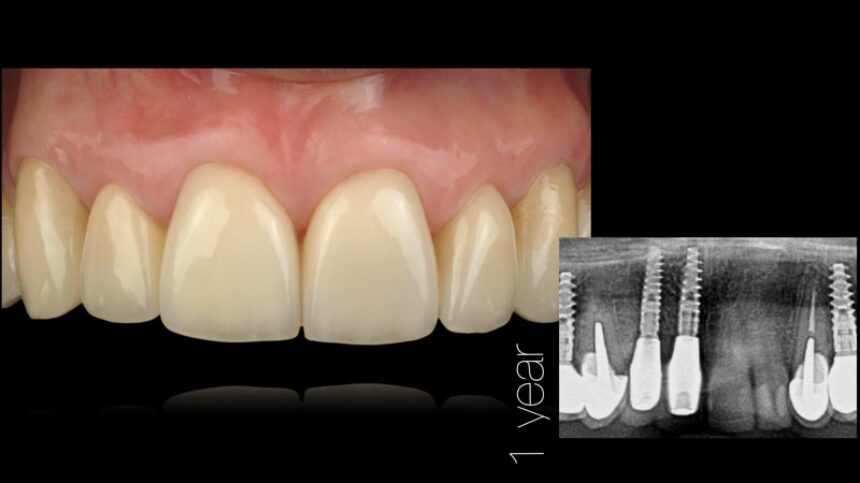

Aesthetic Implant Dentistry – basic science

Anatomical determinants of aesthetic implant restoration – Diagnosis and treatment planning.

Soft Tissue management.

Surgical techniques for hard and soft tissue augmentation.

Long term results after 30 years of experience.